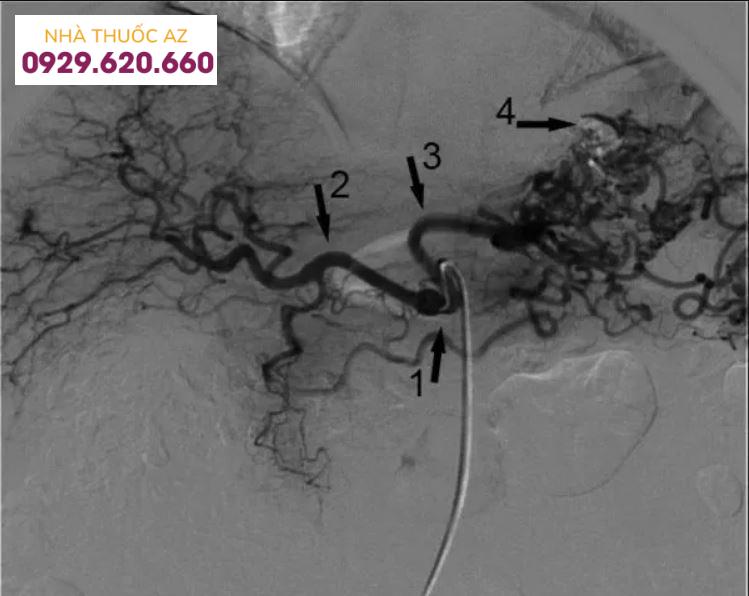

Dùng ống thông và dây dẫn tiếp cận với tĩnh mạch thận trái và vị trí nối thông tĩnh mạch vị – thận trái (gastrorenal shunt).Đưa ống thông có bóng (Forgarty catheter) vào luồng thông tĩnh mạch vị thận. Tiến hành bơm bóng để chặn hoàn toàn dòng chảy của vị trí nối thông tĩnh mạch này.Tiến hành chụp mạch búi tĩnh mạch dạ dày giãn qua ống thông có bóng. Đánh giá toàn bộ hệ thống búi mạch giãn và các nhánh bàng hệ, dẫn lưu.

Nút mạch các nhánh bàng hệ

Dùng vi ống thông (microcatheter) và dây dẫn siêu nhỏ (microguide wire) tiếp cận với các nhánh tĩnh mạch bàng hệTiến hành nút tắc các nhánh tĩnh mạch bàng hệ này bằng vòng xoắn kim loại (Coils).

Hình ảnh giãn tĩnh mạch dạ dày do huyết khối động mạch lách

Nút mạch búi tĩnh mạch dạ dày giãn

Ống thông có bóng (Forgarty catheter) vẫn được giữ trong luồng thông tĩnh mạch vị – thận trái, bóng được bơm căng đến khi chặn được hoàn toàn dòng lưu thông của luồng thông tĩnh mạch này.Đưa vi ống thông vào trong búi tĩnh mạch giãn qua ống thông có bóng.Bơm chất gây xơ hóa, tắc mạch vào trong búi tĩnh mạch giãn qua vi ống thông.Khóa vi ống thông và ống thông có bóng để không cho các chất gây xơ trào ngược trở lại.